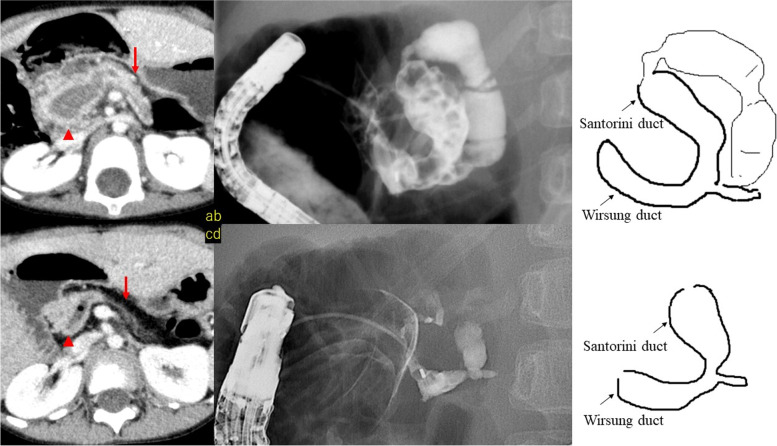

Case 1 was a 3.1-year-old male patient in whom ERCP revealed pancreatic stones and dilatation of the pancreatic duct in the pancreatic head and for whom stone removal was performed. The pancreatic endocrine and exocrine functions of the patient were followed-up on an outpatient basis and, at 6.3 years of age, the patient was found to have decreased exocrine function and atrophy of the pancreatic body and tail. The atrophy was considered to be due to impaired pancreatic fluid drainage. Since papillary balloon dilatation had no effect, placement of a pancreatic duct stent in the pancreatic duct of the pancreatic head was considered to have a high probability of causing long-term withdrawal. The patient underwent pancreatic head and pancreaticojejunostomy at the age of 7 to preserve residual pancreatic function. Thereafter, no postoperative pancreatitis was observed (Fig. 3).

Case 2 showed flexion of the Wirsung duct, and a pancreatic duct stent was placed from the main papilla to the caudal pancreatic duct. Pancreatic stone removal was only performed during the first surgery. Removal of the stent resulted in recurrence of symptoms; thus, the pancreatic duct stent was replaced regularly and the patient was followed-up. Recurrence of symptoms has not been observed for 13 months after stent placement (Fig. 4a and b).

In Case 3, the endoscope could not be inserted into the main papilla and pancreatic stones were not found in the initial ERCP. In addition, we confirmed that drainage of contrast media from the main papilla and accessory papilla was good. However, due to repeated pancreatitis, a dominant dorsal duct was suspected, and a pancreatic duct stent was placed in the caudal pancreatic duct from the accessory papilla. Although regular stent replacement was required thereafter, the patient has been free from pancreatitis for 19 months after the initial stent placement (Fig. 4c and d).

In Case 4, the main papilla could not be identified in the ERCP at the age of 1 year and 8 months, and contrast imaging was performed from the accessory papilla. Pancreaticobiliary maljunction, dilatation of the common bile duct and angulation of the Santorini duct were observed. The patient underwent laparoscopic extrahepatic bile duct resection at the age of 1 year and 10 months, and no recurrence of symptoms has been observed for 4 years (Fig. 4e).

In two patients who underwent accessory papilla imaging, the accessory papilla was regarded as the main papilla during ERCP, and contrast imaging was performed. Three of the four patients had an annular pancreas (Figs. 3 and 4), and it was difficult to visualize the path of the pancreatic duct, even with contrast imaging. In Cases 1 and 3, the path of the pancreatic duct could only be detected on repeated ERCPs.